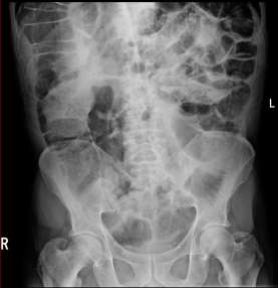

He underwent gastroscopy and colonoscopy which were normal. A CT chest, abdomen, and pelvis was then requested to exclude malignancy. However, it was reported as presence of a long segment of markedly dilated small bowel with air in the bowel wall, which appears to be the ileum. There were no peritoneal or pulmonary deposits and no definite obstructing lesion was visible. There was, however, a suspicious lesion in the ileo-cecal region. The reporting radiologist came to conclusion as distal small bowel obstruction with perforation. CXR and AXR were consistent with the findings of pneumatosis intestinalis.

Figure 1: CXR demonstrated air below diaphragm